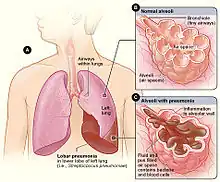

| Figure A shows the location of the lungs and airways in the body. This figure also shows pneumonia affecting the lower lobe of the left lung. Figure B shows normal alveoli. Figure C shows infected alveoli. | |

Lobar pneumonia is a form of pneumonia characterized by inflammatory exudate within the intra-alveolar space resulting in consolidation that affects a large and continuous area of the lobe of a lung.[1][2]

The invading organism starts multiplying, thereby releasing toxins that cause inflammation and edema of the lung parenchyma. This leads to the accumulation of cellular debris within the lungs. This leads to consolidation or solidification, which is a term that is used for macroscopic or radiologic appearance of the lungs affected by pneumonia. Bacterial pneumonia is mainly classified into lobar and diffuse depending on the degree of lung irritation or damage.